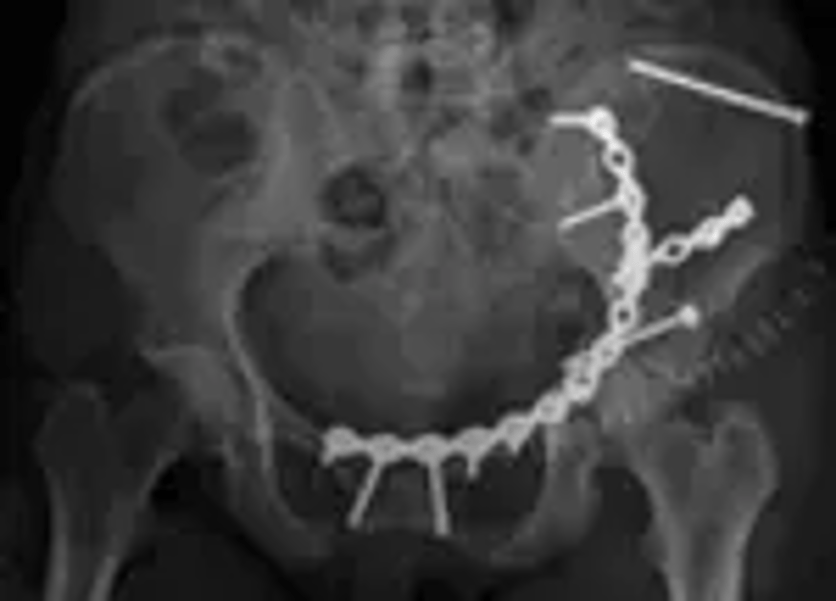

Personer som opererats för svåra bäckenskador efter allvarliga olyckor är relativt nöjda med sin livskvalitet och har i stor utsträckning återgått till sin ordinarie livsföring, visar studier vid ortopedkliniken, Akademiska sjukhuset i Uppsala där man följt denna patientgrupp under flera år.

– Främsta syftet med studierna är att genom systematiserad uppföljning av patienter förbättra vården och omhändertagandet av denna patientgrupp. Skador på bäckenet är ganska ovanliga och allvarliga skador som påverkar personen både fysiskt och psykiskt, säger doktor Tomas Borg, ortoped på Akademiska sjukhuset och ansvarig för studien.

På Akademiska sjukhuset opereras 50-70 personer varje år för svåra bäckenskador, vilket är mer än hälften av alla i landet. De skadade kommer från hela landet, många transporteras hit i ambulanshelikopter. Förutom trafikolyckor är fall från hög höjd, exempelvis från stegar eller på byggarbetsplatser de vanligaste skadeorsakerna